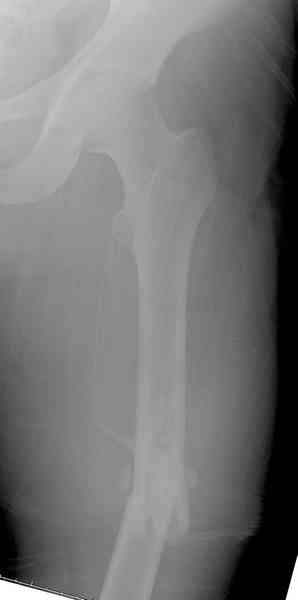

Предыдущей сменой до 4:00 утра по поводу открытого перелома бедра, тибиал плато, пилон и надколенника сделана операция.

Пострадавшему 21 г., травма скоростная, после I&D с расширением раны, на бедре сделана операция ретроградным интрамедуллярным штифтом, остеосинтез с частичной резекцией надколенника и ушивание собственной связки.

На голень наружный фиксатор, рану на бедре ушили (рана была изнутри кнаружи всего 2 см). По протоколу травматических больных, до операции обследован ангиографически, (у больного дистально не смогли определить пульсацию) сосудистый хирург подтвердил проходимость на всем протяжении магистрального сосуда нижней конечности по снимкам ангиограмм.

На следующее утро в 7 часов осмотрен, у больного отсутствовал пульс на a.dorsalis pedis и на a. tibialis posterior, при пассивном движении первого пальца болевой симптом и отсутствовала чувствительность в поространстве между первым и вторыми пальцами.

Сравнительный повторный мониторинг на компартмент синдром, на голени утром давление поднялось до 70 мм, когда послеоперационные были около 30мм.

Срочная фасциотомия на всех 4 компартментах: латерально и медиально,

кстати было достаточно только латеральной фасциотомии, чтобы услышать на допплере пульсацию,

на бедре измерения не подтвердили подозрения на компартмент синдром и рана была закрыта вакуумной губкой (wound VAC).

В настоящее время больной в реанимации по поводу Черепно Мозговой Травмы и состояние улучшается. Запланировал ушивание раны в пятницу, если позволит состояние мягких тканей и при отсутстви отека возможно удастся просунуть перкутанномедиальную пластину.